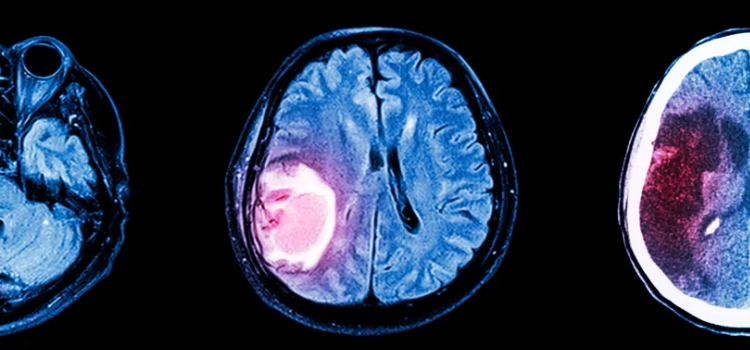

Organoides derivados de pacientes de glioma para personalizar el estudio y futuro tratamiento de estos tumores cerebrales

Los organoides son 'mini-órganos' desarrollados en laboratorio a partir de células humanas, que imitan la actividad de los órganos humanos, lo que facilita la investigación de enfermedades y la búsqueda de posibles tratamientos

En esta investigación, el equipo del ISCIII ha generado organoides tumorales derivados de pacientes afectados de glioma, y ha logrado que 'imiten' con fiabilidad la heterogeneidad celular tumoral, la arquitectura histológica y las firmas moleculares de los tumores 'madre', preservando características clínicamente relevantes, perfiles inmunitarios, estructuras vasculares y las características de cada subtipo tumoral.